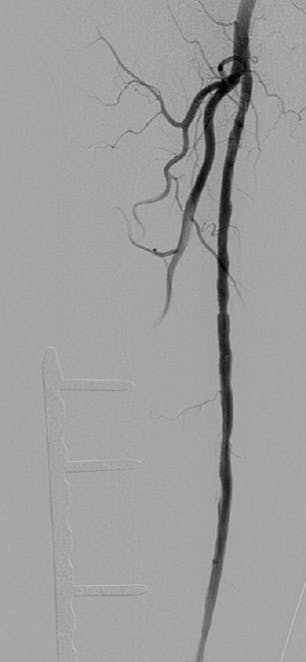

Bilateral common femoral artery access enabled the Pounce™ Thrombectomy System to remove the emboli and reestablish normalized flow without thrombolysis or surgical intervention (Figure 2 and Figure 3). With the Pounce™ Thrombectomy System, multiple vessels or branches of the arterial tree were able to be reopened during the same session.

Figure 2. Arteriogram of right profunda femoral artery (A), right popliteal artery (B), and left tibioperoneal trunk (C) after Pounce™ passes.